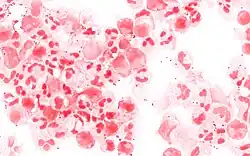

Septicaemia caused by Neisseria meningitidis has received much less public attention than meningococcal meningitis even though septicaemia has been linked to infant deaths.[6] Meningococcal septicaemia typically causes a purpuric rash, that does not lose its color when pressed with a glass slide ("non-blanching") and does not cause the classical symptoms of meningitis. This means the condition may be ignored by those not aware of the significance of the rash. Septicaemia carries an approximate 50% mortality rate over a few hours from initial onset.